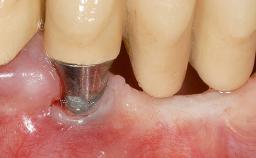

In 1983, a 51-year-old non-smoking patient was referred for the treatment of moderate chronic periodontitis. At the initial examination, 47% of sites exhibited probing depths of 4 to 6 mm. Periodontal therapy consisted of initial periodontal treatment including oral-hygiene instructions and supra- and subgingival debridement, followed by periodontal surgery to eliminate residual pockets.

| # of Teeth | 1 |

| # of Implants | 1 |

| Attachment | One-Piece |

| Soft Tissue Grafting | Simultaneous |

| Abutment Type | Standard |